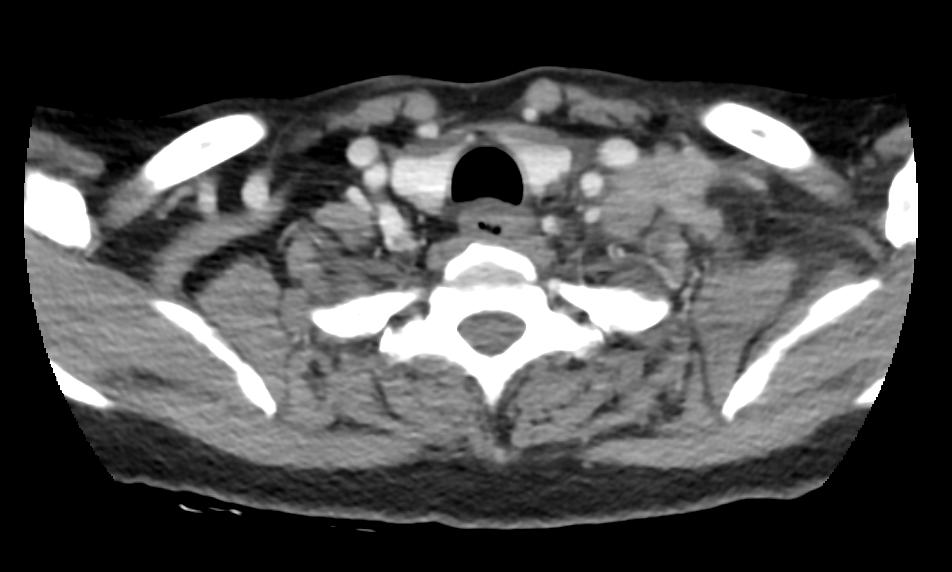

放疗结束3个月后,无意间摸到左侧颈部包块,鸽蛋大小,伴局部胀痛,无发热畏寒,无胸闷胸痛,无腹痛,颈部平扫+增强(2020-07-13 11:08):左侧颈根部V区、锁骨上、左侧腋下多发肿大淋巴结,考虑转移性可能大。患者局部有放疗指征,于2020-08-06针对左侧锁骨上下区以及左侧腋下转移淋巴结以及相关淋巴引流区域行调强放疗,设95% PGTVnd DT5600cGy/200cGy/28f,95% PTV DT5000cGy/200cGy/25f,每周5次,过程顺利,颈部胀痛明显好转,自觉包块较前缩小。因患者身体虚弱,不能耐受化疗,完善血液基因NGS检测,未见明显获益药物靶点,放疗结束后未行特殊治疗。

2020-7-13颈部增强CT